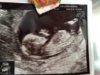

Ultrassa käyty ja tässä kävi juuri niin, kuin vähän jo etukäteen täällä manailin: Koska neuvola ei reagoinut varhaisultran mittoihin EIKÄ myöskään pitkään kiertooni mitenkään (minkä seurauksena siis pikkuinen on viikon jäljessä laskennallisia viikkoja), ei niskaturvotusta voitu mitata ollenkaan. Ultraaja kyllä manaili ihan samaa kuin minäkin, kun kerran olisi ollut kaksikin todistetta asiasta. No, ensi viikolla sitten uudestaan! Muuten asiat olivat oikein hyvin, syke oli normaali ja rakenteet näyttivät hyviltä niiltä osin, kuin niitä pystyi katsomaan :)